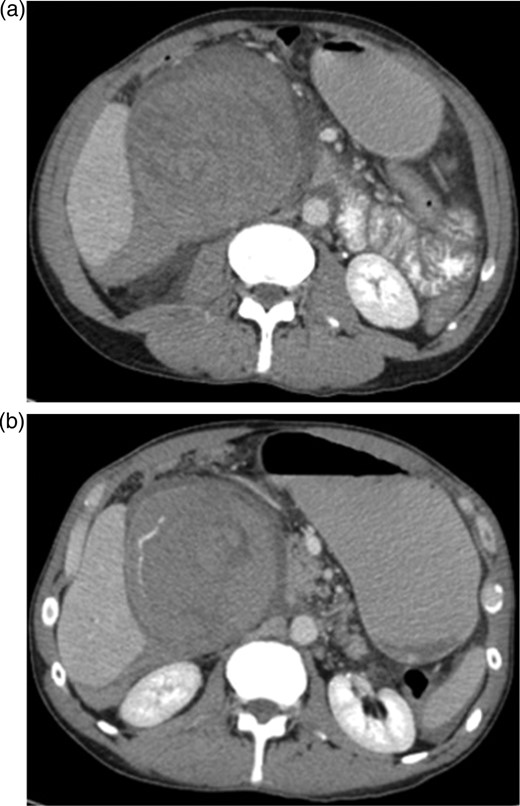

An ultrasound was done showing a mass in the right upper quadrant with no visualization of the gallbladder and no evidence of biliary tree dilatation. Therefore, a CT scan was performed which showed a large haematoma in the gallbladder fossa, which distends the gallbladder wall causing mass effect (Fig. 1a and b). Furthermore, active extravasation of IV contrast was seen. Initially, this was not clear if the haematoma is arising from the liver or within the gallbladder. Given his haemodynamic stability he was taken to the interventional angiography suite for an arteriogram of his abdominal aorta and splanchnic vessels. The bleeding was localized to a branch of the cystic artery and no pseudoaneurysm was identified (Fig. 2). Then, embolization of cystic artery with gelfoam material was performed. Since, embolization of the cystic artery proper was done, the decision was made to explore the patient and perform a cholecystectomy. Prior to the operation the patient became tachycardic at 100 with a systolic blood pressure of 90 and a diastolic of 60. His repeat haemoglobin was 10.1. Appropriate resuscitation with blood transfusion was performed.

(a and b) CT scan upper abdomen showing a large haematoma in the gallbladder fossa, which distends the gallbladder wall causing mass effect.